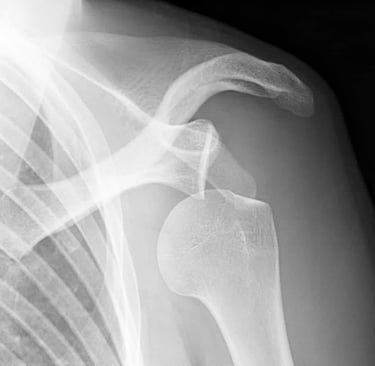

La Butée : Une Solution Efficace

Parmi les interventions chirurgicales, la butée constitue une des solutions les plus efficaces pour traiter l'instabilité chronique. Cette procédure implique le renforcement des structures ligamentaires de l'épaule et la reconstruction des composants endommagés. Ce type d'intervention est généralement considéré lorsque les méthodes conservatrices échouent, surtout chez les sportifs ou les individus très actifs. La réhabilitation post-opératoire est primordiale pour retrouver une fonction optimale de l'articulation.

En conclusion, l'instabilité de l'épaule et les luxations nécessitent une attention particulière et un diagnostic précis pour déterminer le traitement adéquat. Les interventions, qu'elles soient conservatrices ou chirurgicales comme la butée, visent à rétablir la stabilité et la fonction de l'épaule, permettant ainsi aux patients de reprendre leurs activités avec confiance.